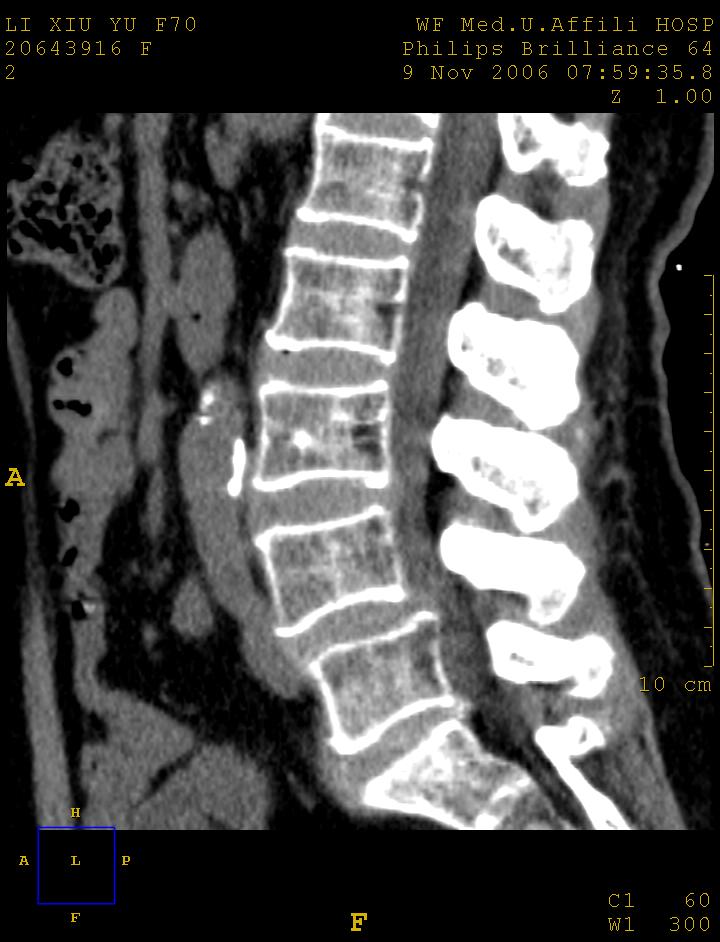

标题: CT5427:女,70岁,腰痛,清晰明了 [打印本页]

女,70岁,腰痛

l4以上向前滑脱

1腰椎骨质增生,2l4向前滑脱,3腰5-骶一椎间盘退变

l4椎体向前滑脱,椎弓裂

l3/4,l4/5,l5/s1椎间盘病变,l4以上向前ι度滑脱并椎小关节交锁、椎弓峡部断裂,椎小关节变性.

考虑:1、腰4假性前滑脱(1度,小关节退行性性骨关节病所致);

2、腰5--骶1椎间盘退行性变。

1、腰4椎体1度滑脱。2、腰椎及椎小关节退行性骨关节病。3、腰3-骶1椎间盘病变。

1腰椎骨质增生,2l4向前滑脱(假性,矢状位椎弓峡部连续),3腰5-骶一椎间盘退变,4小关节面综合征

1 腰4椎弓崩裂,腰4椎体向前ι度滑脱并椎小关节交锁,腰4/5小关节明显增生硬化,间隙内可见真空征。

2 腰椎间盘不同程度膨出,腰4/5、腰5/骶1椎间盘突出,腰4/5椎间隙变窄,腰5/骶1间盘变性(间隙内可见真空征)。

3 诸椎体缘不同程度骨质增生,腰5、骶1后骨刺明显,腰5椎体后上缘可能有软骨结节(由于没有平扫,不易确定)。

4 椎体前缘可见主动脉壁钙化。

诊断:腰椎退行性骨关节病。